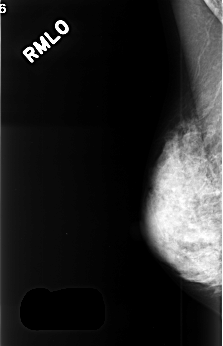

C_0375_1.RIGHT_MLO

RIGHT_CC LINES 4592 PIXELS_PER_LINE 2880 BITS_PER_PIXEL 12 RESOLUTION 50 NON_OVERLAY

RIGHT_MLO LINES 4496 PIXELS_PER_LINE 2896 BITS_PER_PIXEL 12 RESOLUTION 50 NON_OVERLAY